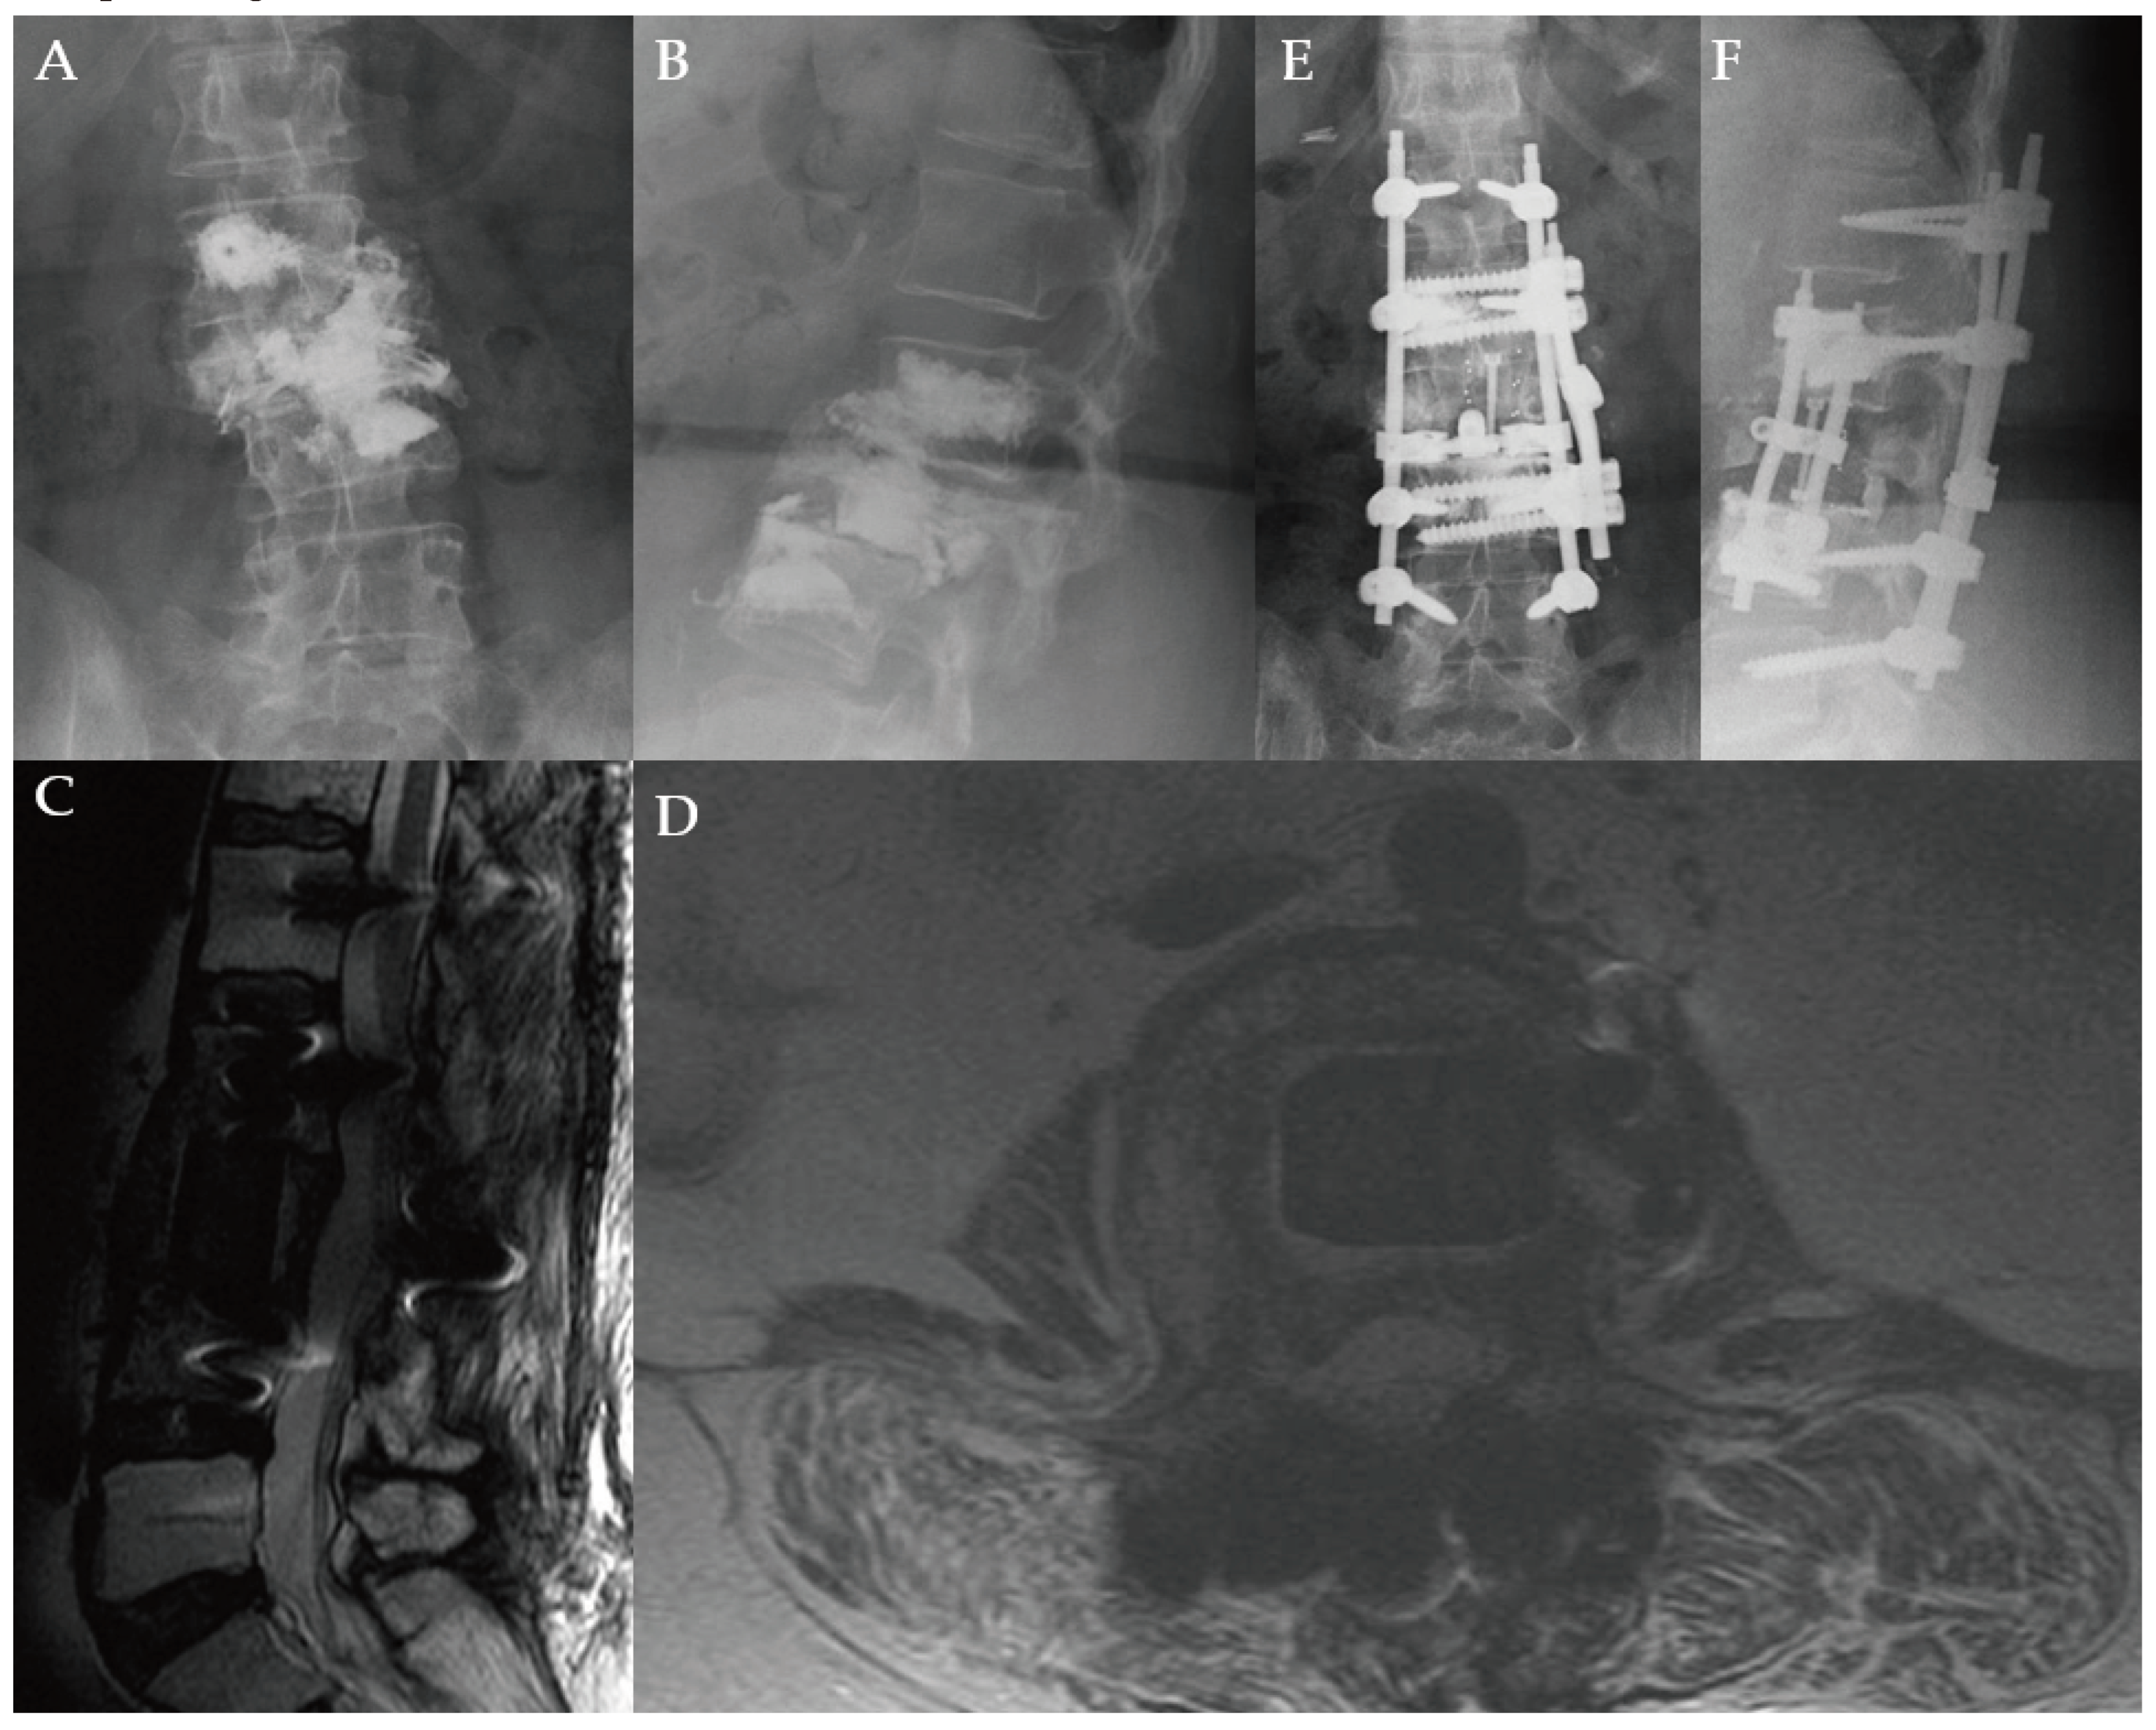

Figure 1. Images of a 69-year-old male with a history of metastatic prostate cancer. He was neurologically intact but was beset with severe back pain 6 years after initial diagnosis. He had evidence of extensive metastatic disease to the entire spine, particularly to T11, as demonstrated by CT (A) and T2-weighted MRI in the sagittal (B), and axial (C) views with concerns for cord compression. He underwent separation surgery with posterior instrumentation. Lateral plain radiograph (D) obtained one day after surgery demonstrates instrumentation spanning T8 to L1. Imaging 3 years later obtained for progressively worsening mechanical back pain shows worsening kyphosis on CT (E) and MRI (F). Patient was scheduled for revision surgery but passed away over 3 years after his index operation.

SM can become symptomatic from mechanical back or neck pain, compression of the spinal cord and neural elements, or lead to the development of pathologic vertebral compression fractures (VCF) and/or spinal instability [7,10]. The latter two often result in debilitating mechanical pain with disabling neurological symptoms and sensorimotor dysfunction. This can lead to worsened overall prognosis and markedly decreased quality of life [7,10,11]. Patchell’s sentinel trial in 2005 established the surgical standard of care for SM as surgical decompression followed by adjuvant RT with the goal of restoring neurological function [12]. More recently, this treatment paradigm has evolved to circumferential tumor debulking with or without instrumented fusion for the goal of spinal decompression to create a safe distance between the tumor and the spinal cord for subsequent spinal stereotactic RT [13]. This approach, coined “separation surgery,” was primarily adapted as a palliative modality, allowing for patients to resume systemic treatments earlier. Its minimally invasive footprint reduces intraoperative and postoperative complications in terminally ill and/or frail cancer patients while restoring and/or preserving neurological function [14,15,16,17]. Posterior decompression is a less invasive, yet time-proven method for decompression of neural elements. However, posterior decompression even with instrumentation can fail to maintain spinal alignment and result in poor functional outcome in a select cohort of SM patients (Figure 1).

Currently, the standard surgical treatment for symptomatic SM with ESCC is separation surgery. While the minimal footprint of separation surgery allows patients to resume systemic therapy earlier, the continued improvement in cancer survivorship means such an approach could predispose a select cohort of patients to redo surgeries and/or recurrent radiation treatments (due to local tumor recurrence). Furthermore, it can also result in significant long-term disability and loss of functional independence from chronic pain symptoms as it doesn’t restore spinal alignment and does not achieve circumferential stabilization, resulting in worsening kyphotic deformity and hardware failure (Figure 1) [9,18,19]. In oligometastatic spinal disease patients with good functional status and favorable long-term prognosis, corpectomy with fusion can allow for maximal tumor debulking for improved local disease control, restoration of spinal alignment, and spinal stabilization for long-term pain relief, functional independence, and improved disease-free survival (Figure 7). This study examines corpectomy in selected SM patients for decompression of neural elements and spinal column reconstruction while focusing on the safety, efficacy, and outcomes.